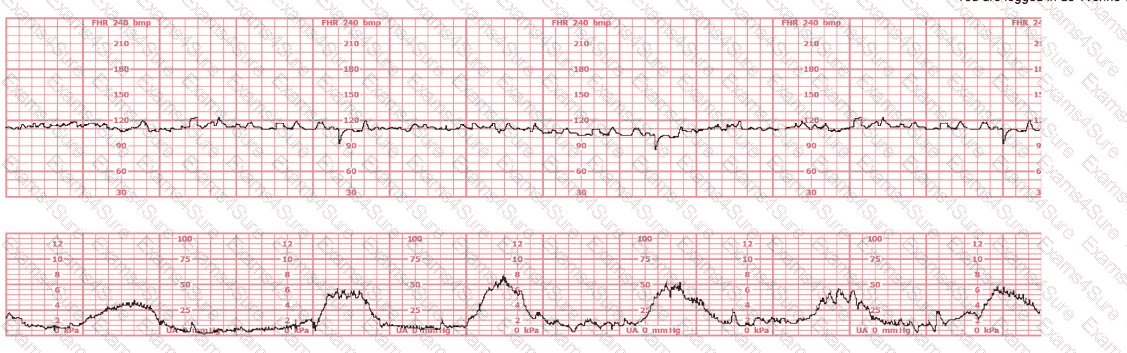

A 30-year-old woman (G2P0) is experiencing preterm labor at 26-weeks gestation. She is receiving magnesium sulfate for neuroprotection. Her external fetal monitoring tracing over the past 30 minutes is shown. The next step would be to: